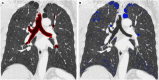

Quantitative analysis of airways and pulmonary emphysema can be done with commercial software, in order to quantify the extent of the disease and to differentiate the contribution of small airways and emphysema in COPD (Courtesy of Lucio Calandriello)

Fig. 12